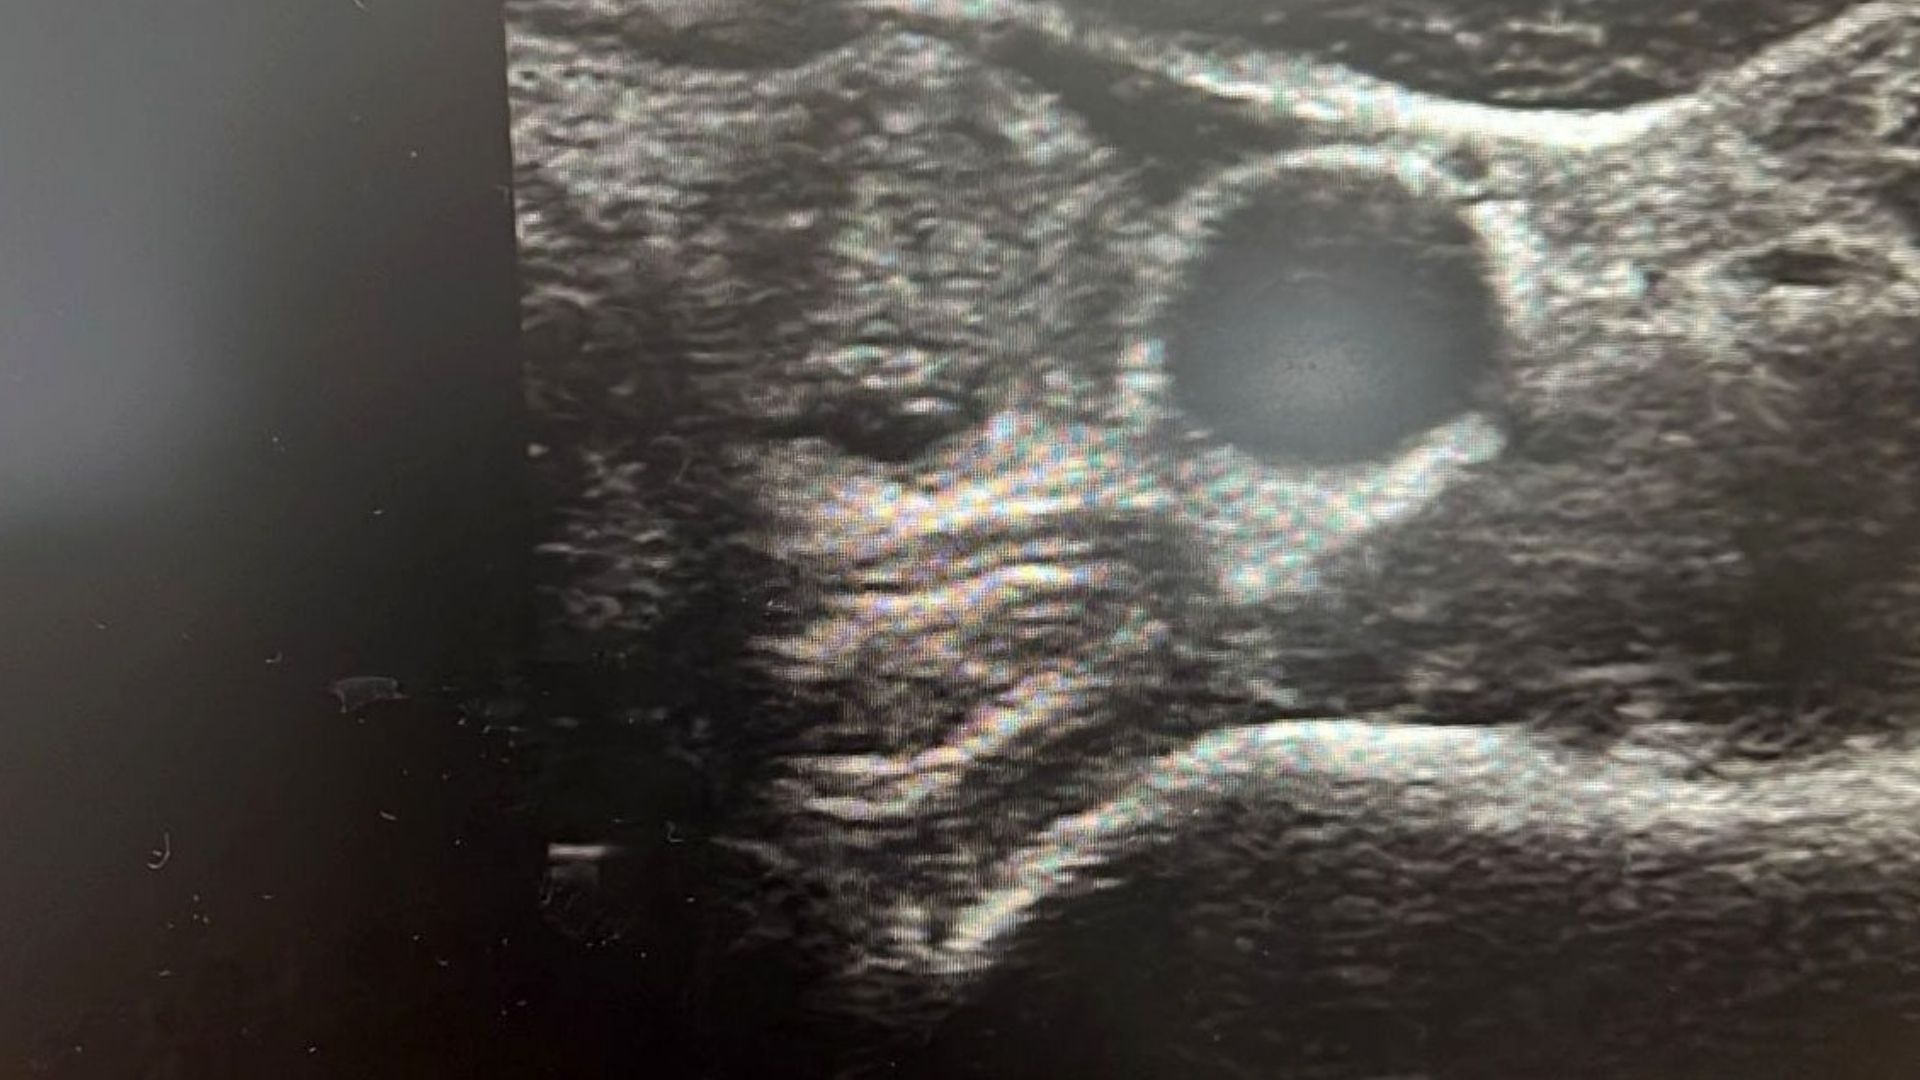

Dr. Demir, tiroit nodüllerinin ses kısıklığı, yutma güçlüğü ve nefes darlığı gibi belirtilerle ortaya çıkabileceğini, ancak çoğu zaman fark edilmeyip ultrason kontrolleriyle saptanabildiğini söyledi. Nodüllerin yüzde 10 ila 20’sinin kötü huylu olabileceğini belirten Demir, erken teşhisin önemine dikkat çekti.